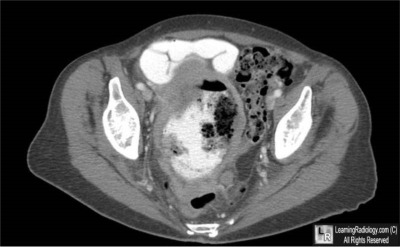

Additional Images-Axial CT Scan of Abdomen and Pelvis

Axial CT Scan of Abdomen and Pelvis

5. Small Bowel Lymphoma

Small Bowel Lymphoma

- Mesenteric involvement by lymphoma may occur by

- Direct extension from bowel

- Indirectly by displacement due to mass effect